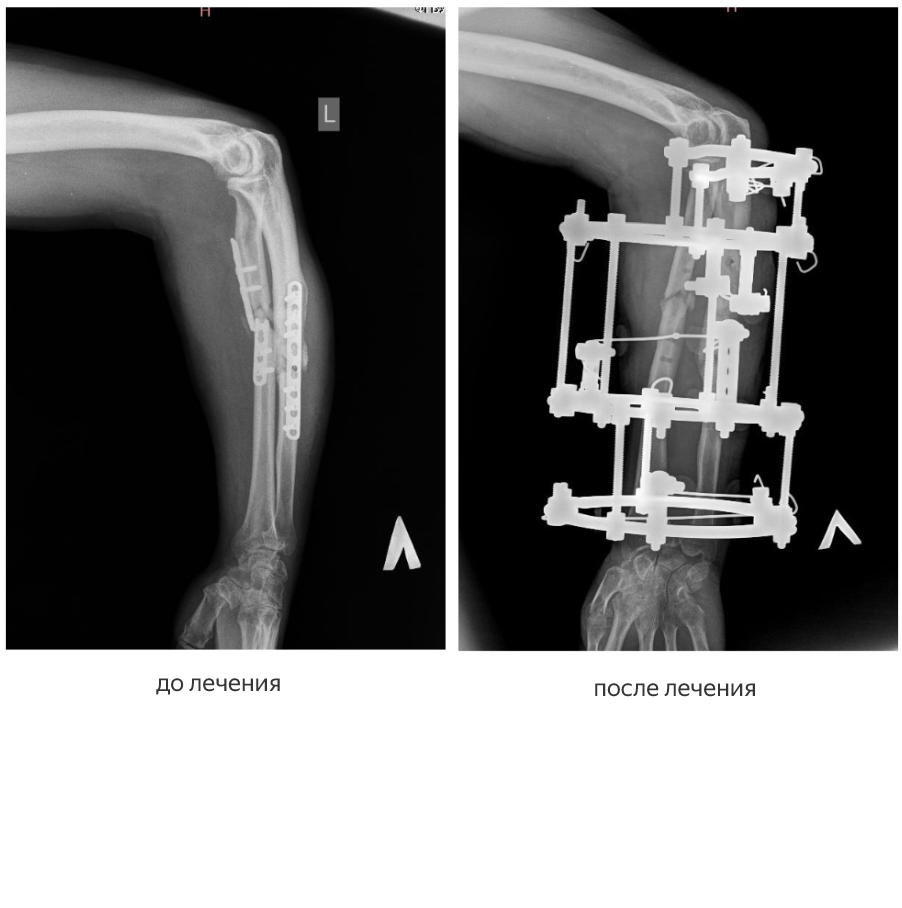

Первый пациент — участник специальной военной операции — поступил в центр с диагнозом «ложные суставы лучевой и локтевой костей предплечья». Лечение проходило в два этапа.

Как рассказал заведующий отделением № 3, врач-травматолог-ортопед высшей категории Виталий Нарицын, в декабре 2025 года мужчине удалили ранее установленные сломанные накостные пластины и выполнили остеосинтез аппаратом Илизарова.

«Эта операция носила подготовительный характер: пластины располагались с ладонной поверхности предплечья, их удаление осложнялось большим массивом мягких тканей, к тому же сами пластины были сломаны, — пояснил Виталий Нарицын. — Мы удалили пластины и зафиксировали предплечье аппаратом Илизарова, чтобы обеспечить заживление раны и подготовить конечность ко второму этапу оперативного лечения».

Второй этап прошел в марте 2026 года. Хирурги перепровели элементы фиксации, выполнили перемонтаж аппарата и полностью восстановили правильную ось лучевой и локтевой костей. Сейчас пациент выписан на амбулаторное лечение по месту жительства. По оценке врачей, кости стабильно зафиксированы, ось конечности правильная.

Оба случая — пример успешного применения метода чрескостного остеосинтеза по Илизарову, позволяющего исправлять даже самые сложные посттравматические деформации, которые не удалось вылечить традиционными способами.